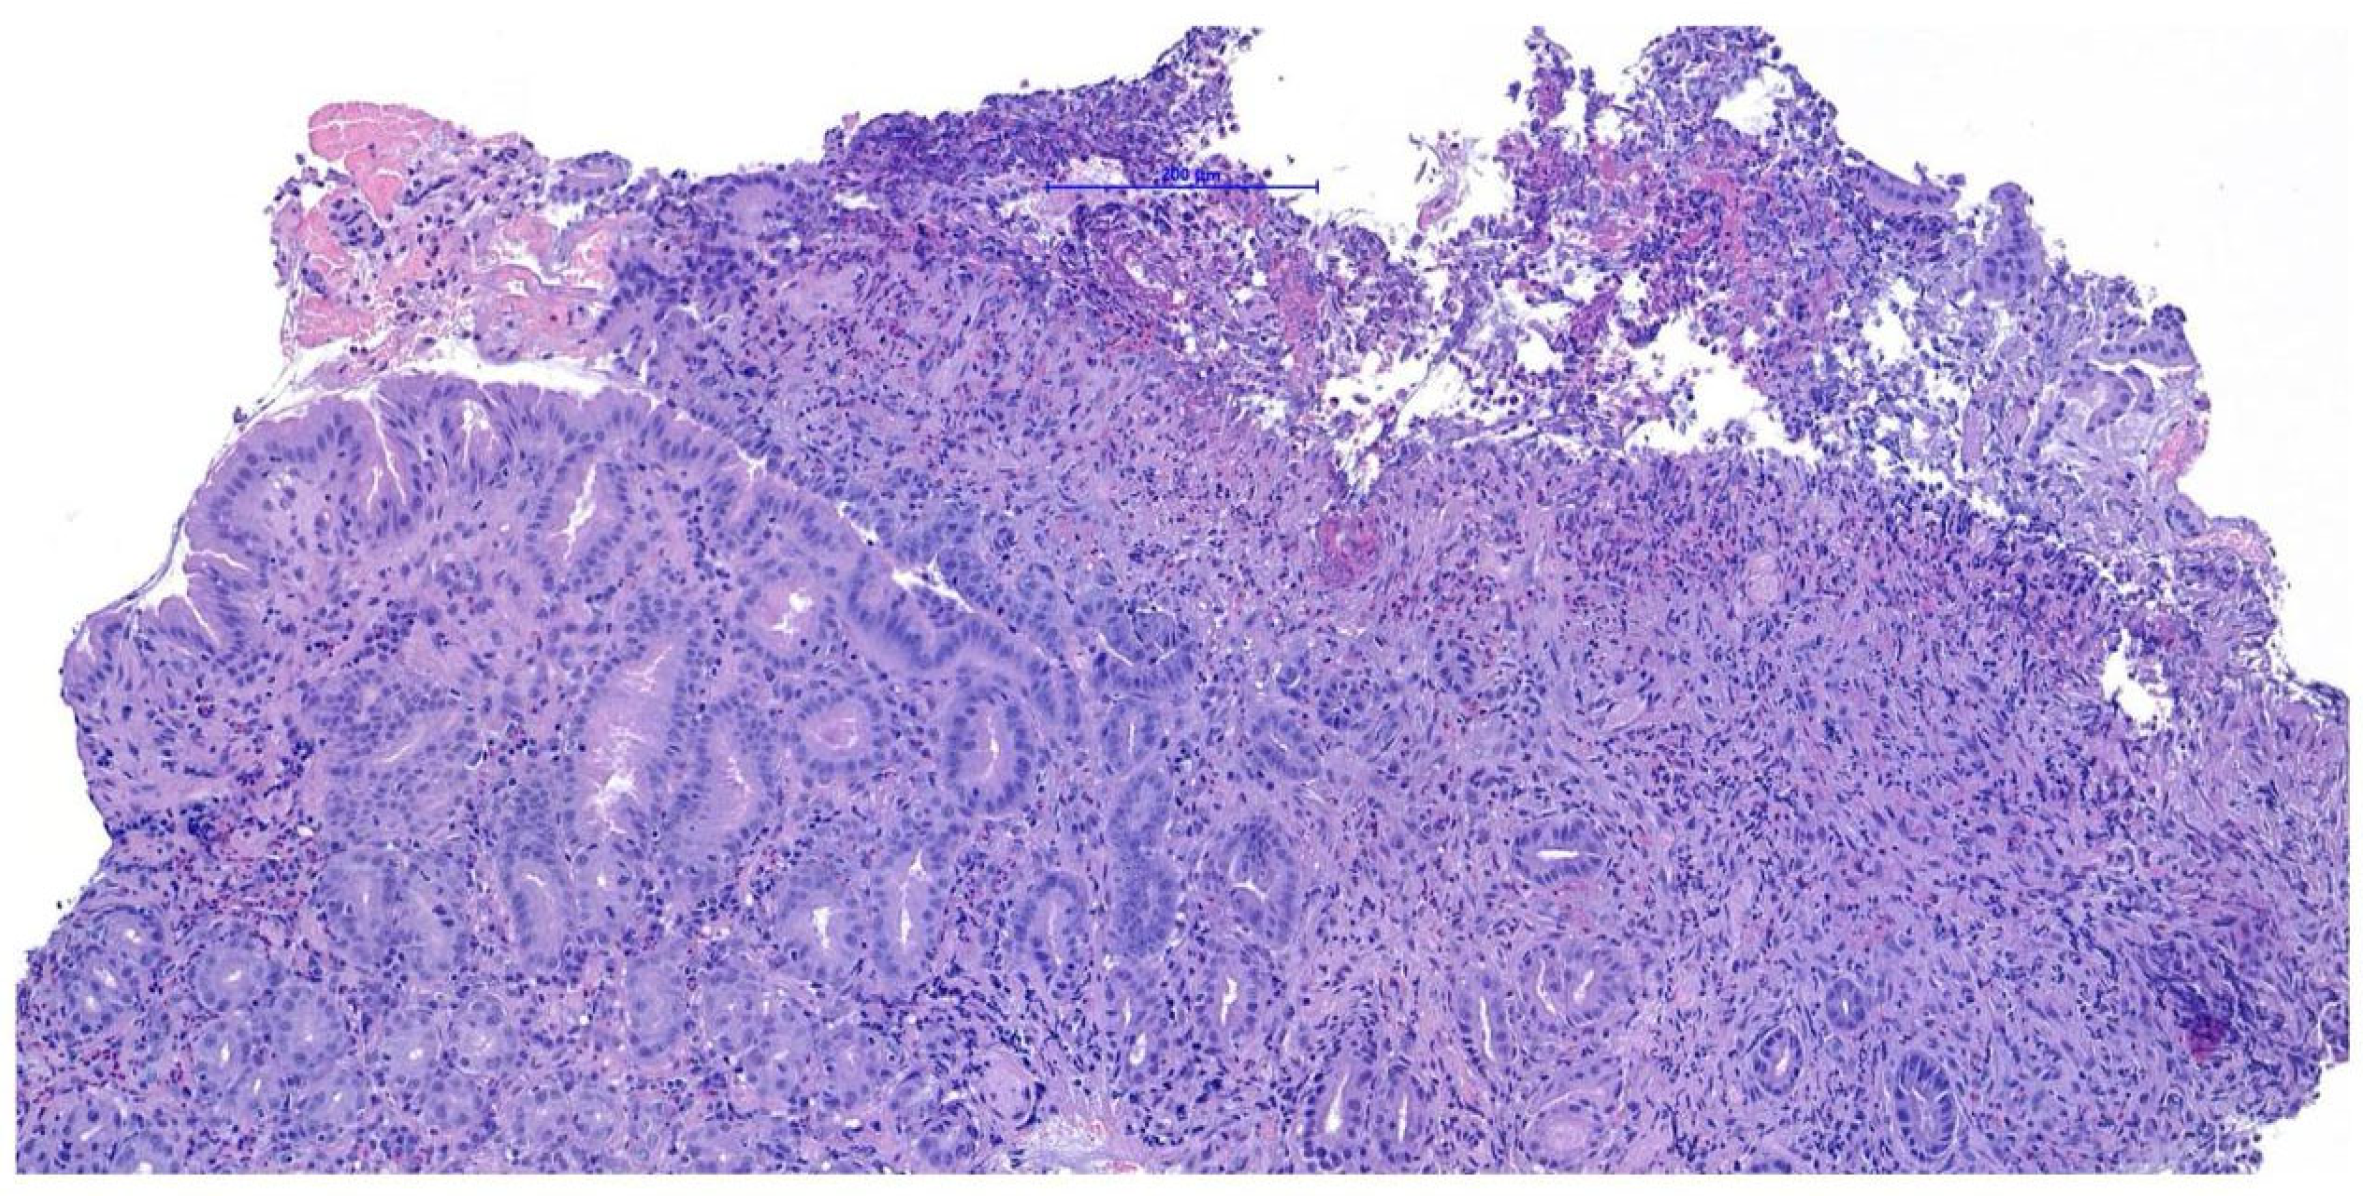

Endoscopy, performed using a flexible veterinary gastroduodenoscope (outer diameter 7.9 mm, Karl Storz Silver Scope 60714NKS), confirmed the presence of a submucosal sessile mass partially obstructing the duodenal lumen (Figure 1). It was not possible to fully advance the endoscope beyond the lesion for a complete duodenal evaluation; however, the mucosa visible just distal to the mass displayed shortened and edematous villi. Thanks to the small diameter of the biopsy forceps, it was possible to pass beyond the lesion endoscopically and obtain samples from the duodenal tract immediately distal to the mass. Additional biopsies were taken from the mass itself and from the gastric mucosa, which showed diffuse follicular hyperplasia, using 2.4 mm fenestrated biopsy forceps (Alton AF-D2421BT).

Histopathological examination of the gastric biopsies revealed mucosa with deep, hyperplastic crypts and occasional erosive and ulcerated areas replaced by necrotic and collagenous material containing abundant eosinophils, together with a mixed inflammatory infiltrate of neutrophils, small lymphocytes, and scattered eosinophils. Duodenal biopsies, including those obtained distal to the mass, showed irregular, shortened and fused villi with a moderate mixed lymphoplasmacytic infiltrate containing neutrophils and eosinophils in the lamina propria. Histopathological examination of the duodenal mass revealed a sample devoid of recognizable microanatomical architecture, composed of fibrocollagenous tissue interspersed with densely cellular areas (Figure 2). Overall, the findings were consistent with eosinophilic and fibroplastic gastroenteritis compatible with feline gastrointestinal eosinophilic sclerosing fibroplasia (FGESF).

Figure 1. Endoscopic view of the duodenal mass.